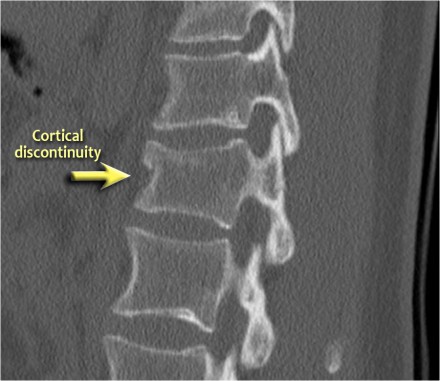

The images show a compression fracture.

All we see is a cortical disruption in the upper anterior wall of the vertebral body and slight loss of height ventrally.

The posterior vertebral cortex is intact.

The sagittal reformatted image also shows the cortical disruption.

Notice that on a 2.5mm axial slice you can miss these fractures.

You have to look at the thin slices to detect such a subtle fracture.